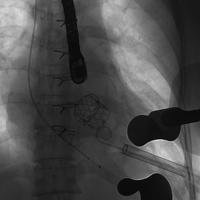

病例二(经心尖二尖瓣瓣中瓣)

患者女性,60岁,既往行二尖瓣生物瓣置换术,置入HANCOCK II 25#瓣膜一枚。STS评分8.18 %,属于外科换瓣手术高风险患者。术前心脏超声示原二尖瓣生物瓣衰败,瓣叶明显脱垂,关闭极差,可及大量反流。术前充分评估,经心尖途径植入23# Renato球扩式瓣中瓣,释放成功后瓣膜功能良好,无明显瓣中及瓣周反流,平均跨瓣压差2.6mmHg。

瓣膜释放 术后左室造影